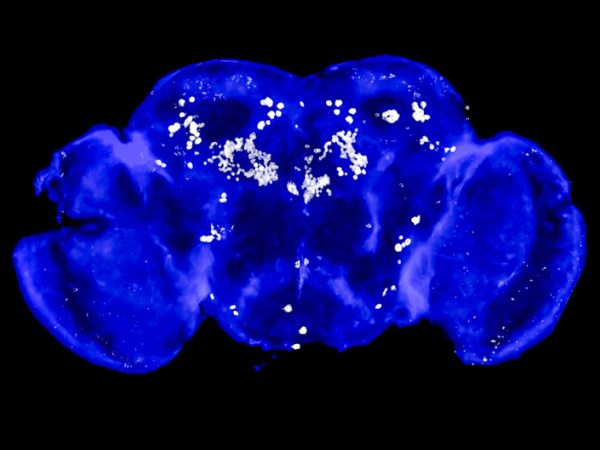

Two years after traumatic brain injury, Grayson Pope continues to make great strides during recoverySeptember 18, 2025More than two years ago, 19-year-old Grayson Pope was fleeing a pop-up storm while playing golf with friends when a large tree collapsed on his golf cart. He suffered hundreds of brain bleeds, brain stem damage and swelling on his brain. -

From employee to patient, UAB employee recovers from TBI after motorcycle accidentAugust 26, 2025After a motorcycle accident, Kristen Davison had a traumatic brain injury that involved facial fractures and bleeding in and around the brain. -